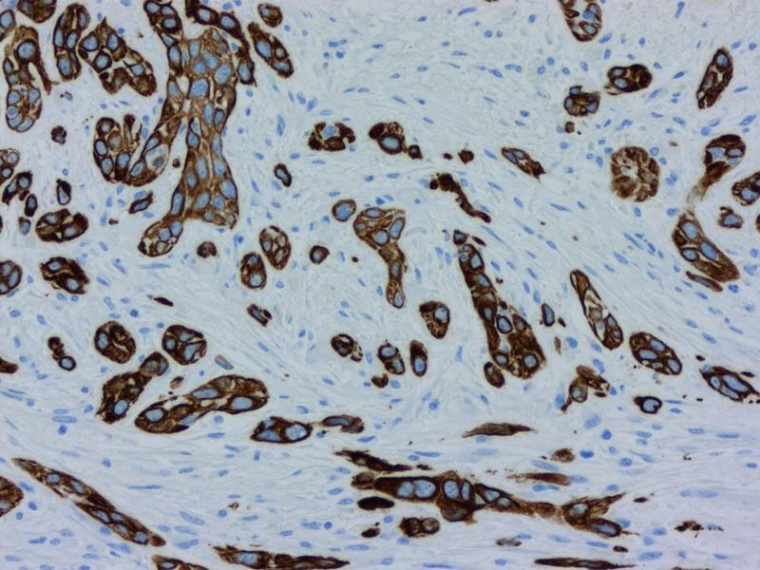

Bauchspeicheldrüsenkrebs gehört nach wie vor zu den tödlichsten Krebsarten überhaupt. In Deutschland werden dieses Jahr voraussichtlich rund 21.000 Menschen die Diagnose erhalten. Davon erliegt die Hälfte innerhalb des ersten halben Jahres der Krankheit, nur zehn Prozent überleben fünf Jahre. Neben der späten Diagnose ist eine der größten Hürden bei der Behandlung von Bauchspeicheldrüsenkrebs die erstaunliche und einzigartige Fähigkeit der Tumorzellen, sich der Behandlung zu widersetzen, indem sie ihre molekulare Identität ändern.